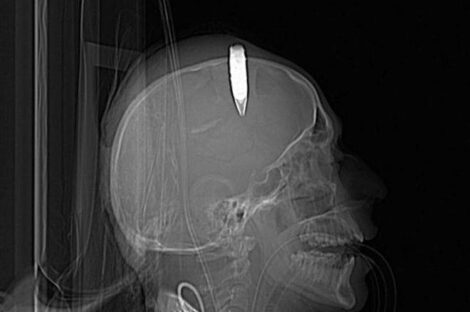

عين ليبيا نجح فريق طبي ليبي بمستشفي على عمر عسكرلامراض وجراحة المخ والاعصاب والعمود الفقري مكون من الدكتور...